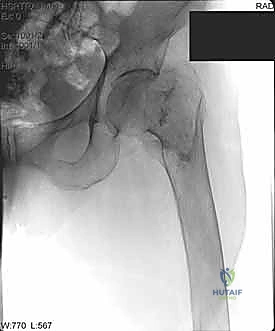

التصوير الطبي المتقدم

- الأشعة السينية (X-rays): هي المعيار الذهبي الأولي. يتم أخذ صور من الأمام للخلف (AP) وصور جانبية (Lateral) للحوض والورك المصاب. تكشف هذه الصور عن موقع الكسر، نوعه (بسيط أم مفتت)، ودرجة الإزاحة.

مجموعة من الصور الإضافية التي توضح مراحل دقيقة من العمل الجراحي المعقد الذي يجريه الأستاذ الدكتور محمد هطيف لضمان أعلى درجات الدقة الميكانيكية الحيوية: